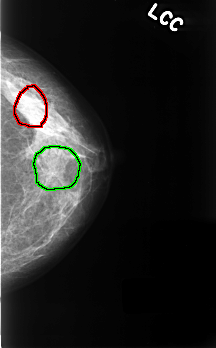

FILE: C_0335_1.LEFT_CC.OVERLAY

TOTAL_ABNORMALITIES 2

ABNORMALITY 1

LESION_TYPE CALCIFICATION TYPE FINE_LINEAR_BRANCHING DISTRIBUTION LINEAR

ASSESSMENT 4

SUBTLETY 4

PATHOLOGY BENIGN

TOTAL_OUTLINES 1

BOUNDARY

ABNORMALITY 2